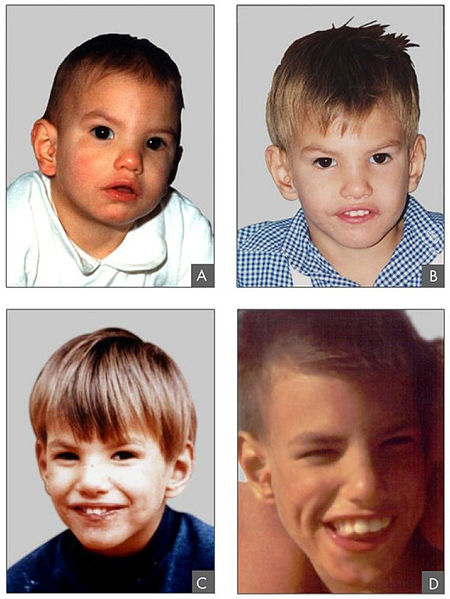

7- Síndrome de Wolf Hirschhorn

El síndrome de Wolf Hirschhorn se caracteriza por una afectación multisistémica, dando lugar a graves trastornos mentales y del crecimiento.

Buena parte de los afectados fallecen durante la fase prenatal o neonatal, pero algunos con una afectación moderada puede llegar superar el año de vida.